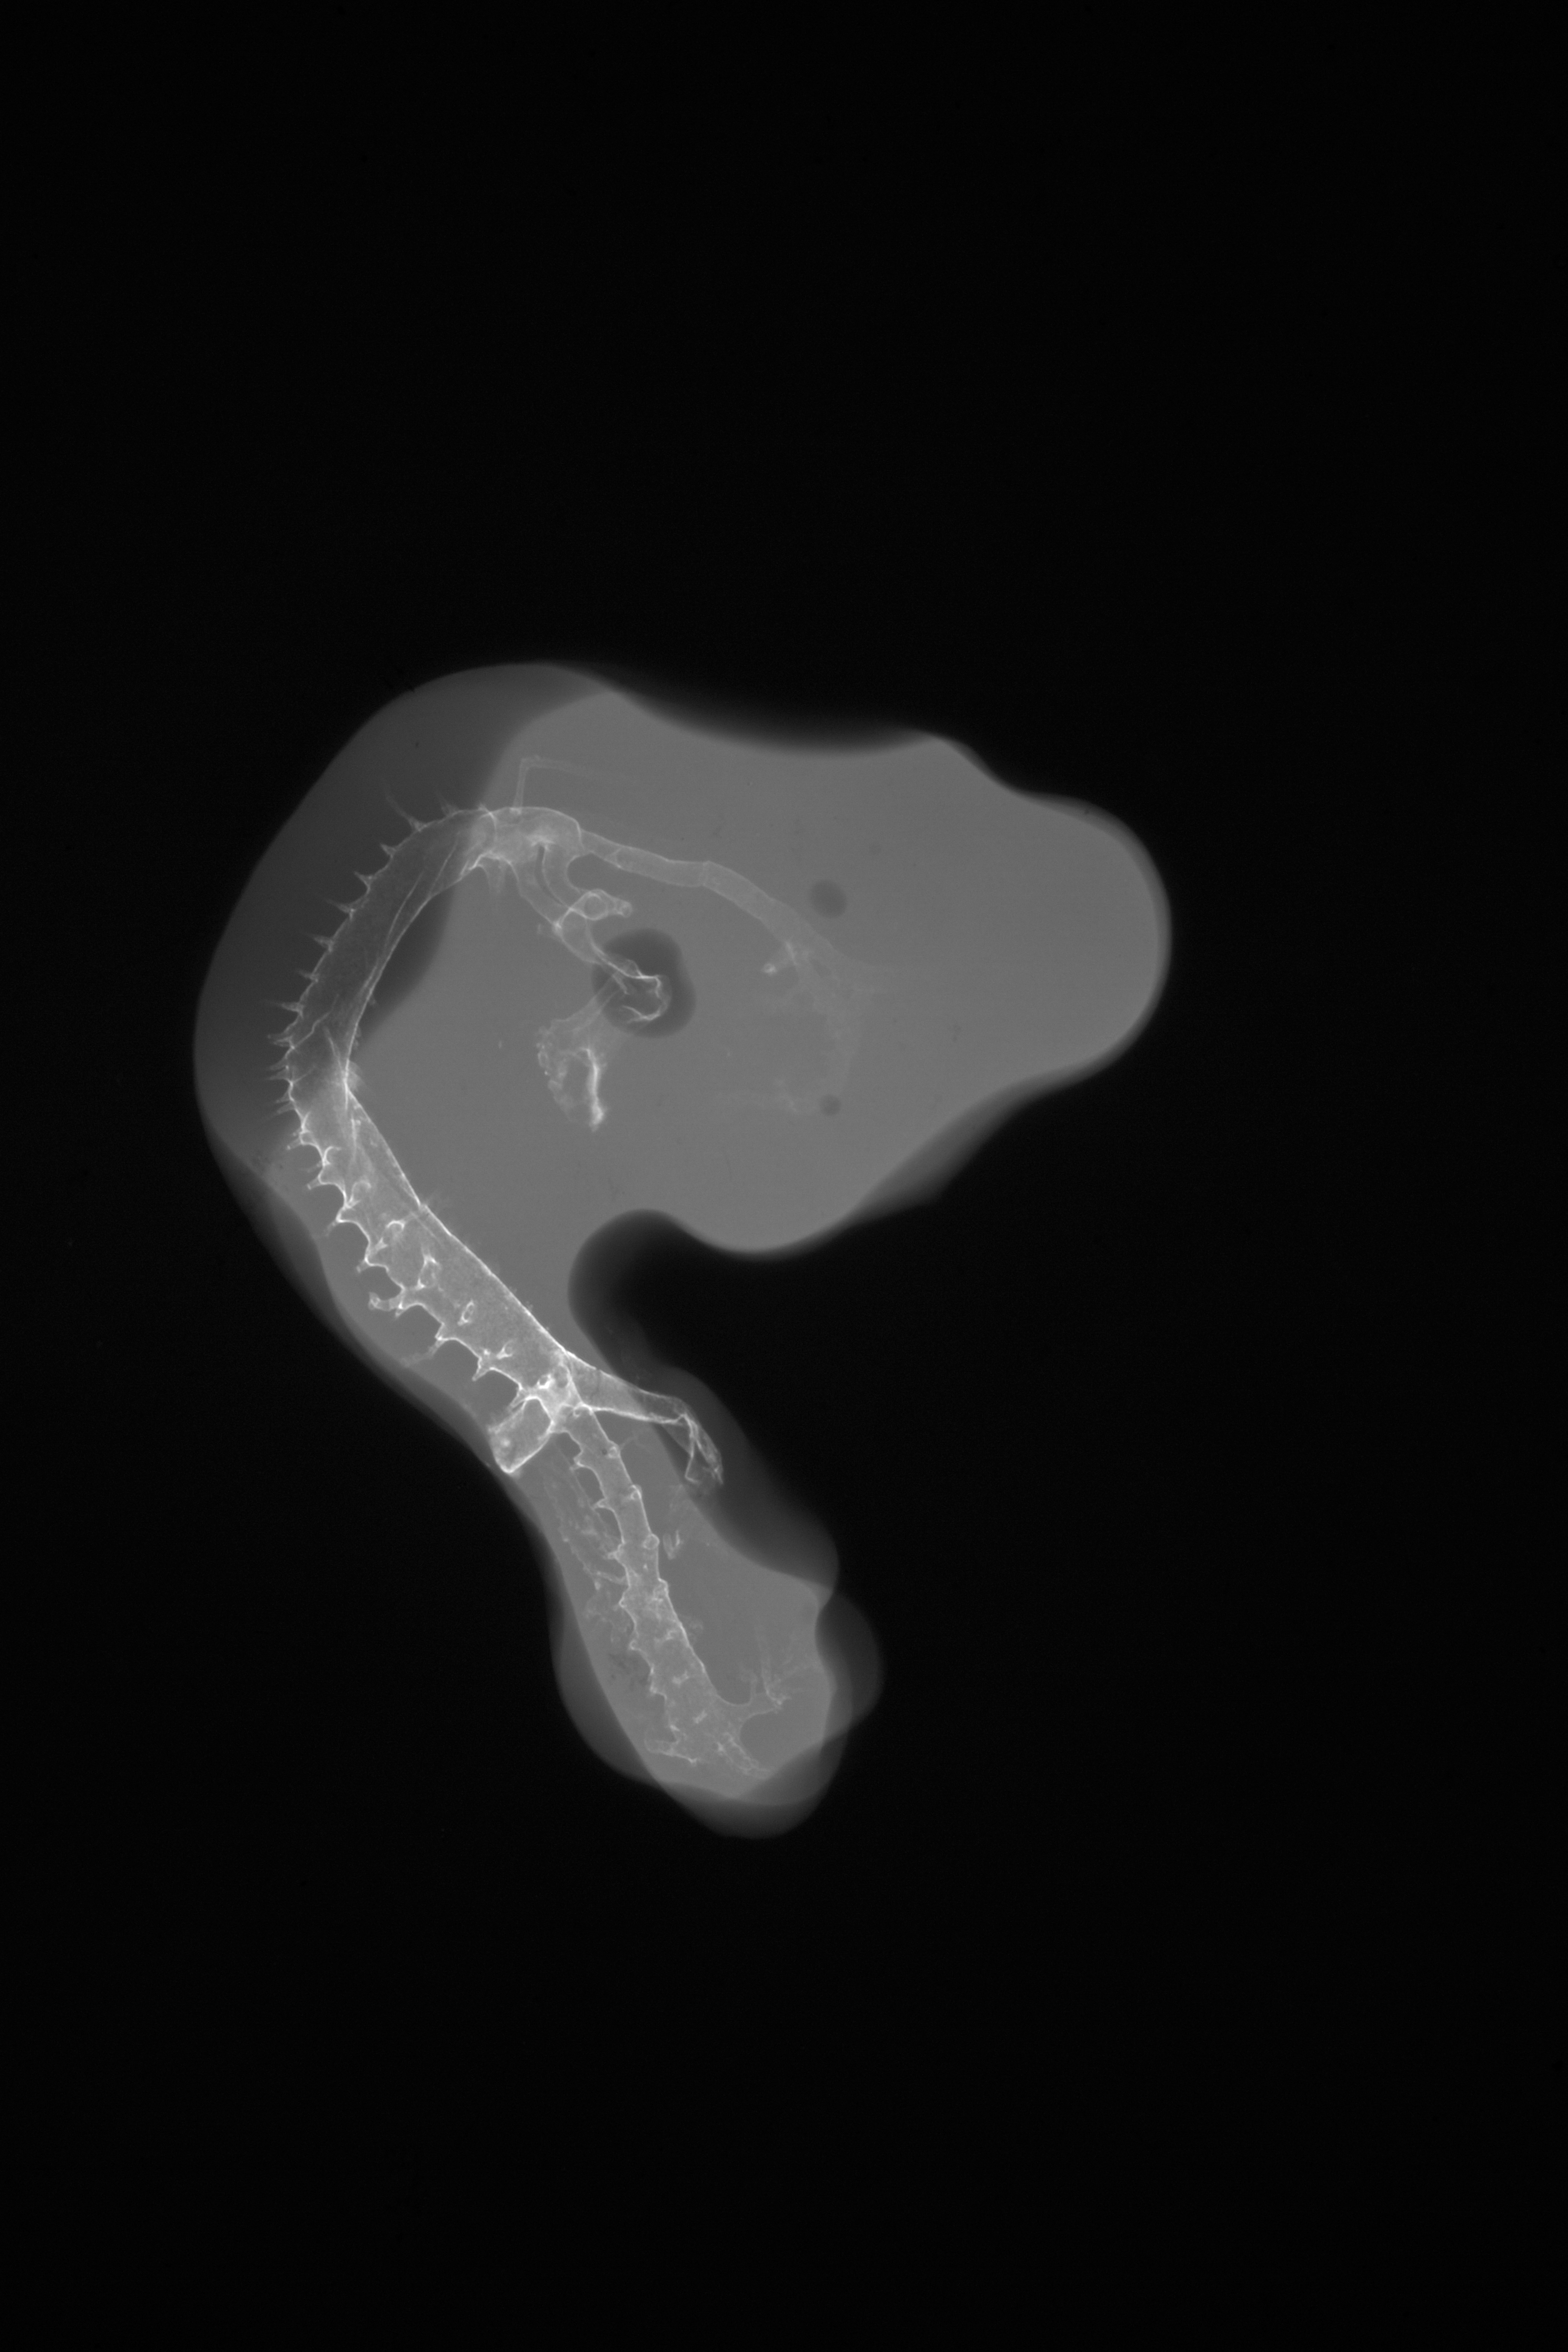

Chick Embryo Microangiography

Hamburger-Hamilton (HH) Stage 20 (approx. 3 - 3.5 days)

X-Ray Micrographs